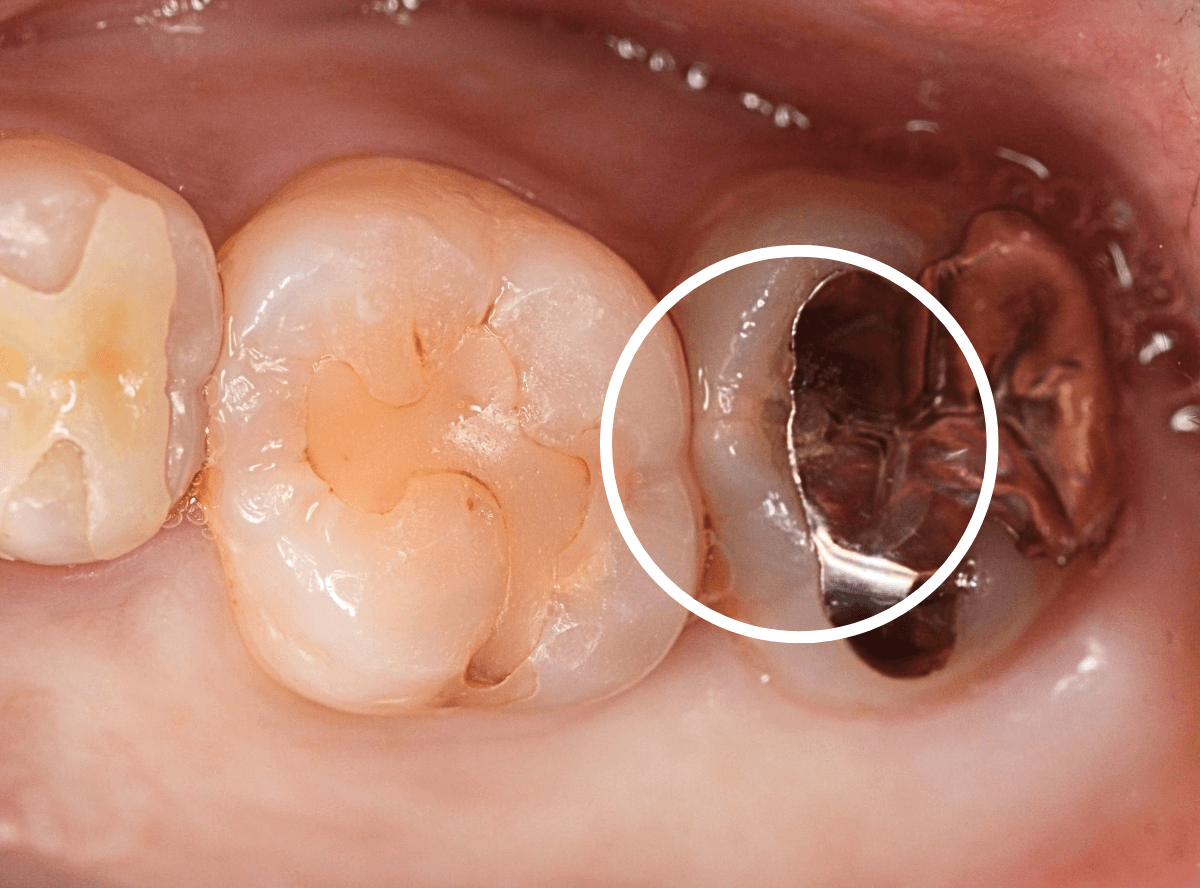

Case.7 劣化した金属の下がひどい虫歯

今回は、歯が欠けたという事で来院された患者さんです。

つめものの中で虫歯が大きく進行してしまい、何かの拍子に歯が欠けてしまった状態です(左側)。

右隣の歯もつめものが劣化して中に虫歯が進行しているのが見えます。

早速、虫歯の治療を開始すると、想定通り虫歯で歯の中はボロボロになっています。

虫歯を取りきったところで、歯の神経が部分的に露出し、出血が見られました(露髄)。

かなり厳しい状況で、どうするか悩むところでしたが・・・。

幸い、神経からの出血も少なく、神経が露出している範囲も小さかったため、神経を残せる可能性に賭けて、神経を保存する処置をしました。

隣の歯の虫歯の処置をしながらの経過観察になります。

痛みが出ませんように。。。